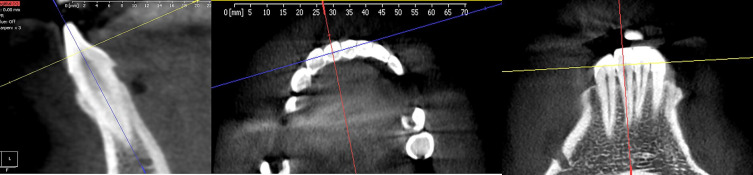

Purpose: The study aimed to measure the distance from the cementoenamel junction (CEJ) to the alveolar bone crest on both the buccal and lingual sides of the anterior mandibular teeth utilizing cone beam computed tomography (CBCT).

Materials and methods: Cone-beam computed tomography (CBCT) was utilized to measure the distance between CEJ and the alveolar bone crest on both the buccal and lingual sides of the mandible's anterior teeth.

Abstract Image